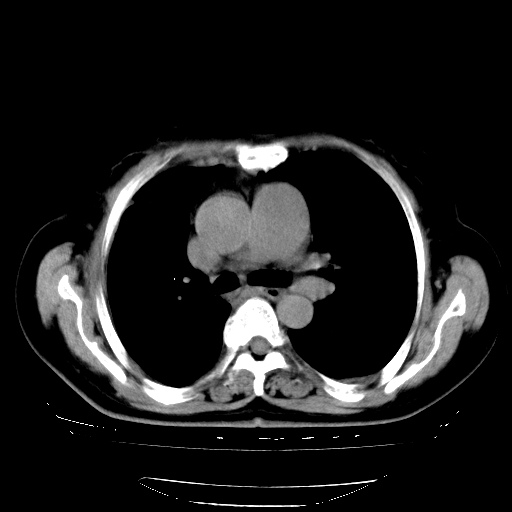

以下是引用zhangzhongshou在2008-3-22 12:52:00的发言:[br]1、右侧液气胸。[br]2、腹水。建议进一步检查。

以下是引用鲁巨ct在2008-3-22 14:10:00的发言:[br]1、右侧液气胸,右中下叶节段性不张。[br]2、腹水,建议上腹部ct检查

以下是引用zjzjr在2008-3-22 17:19:00的发言:[br]1、右侧液气胸,右下叶节段性不张。[br]2、腹水,建议上腹部ct检查